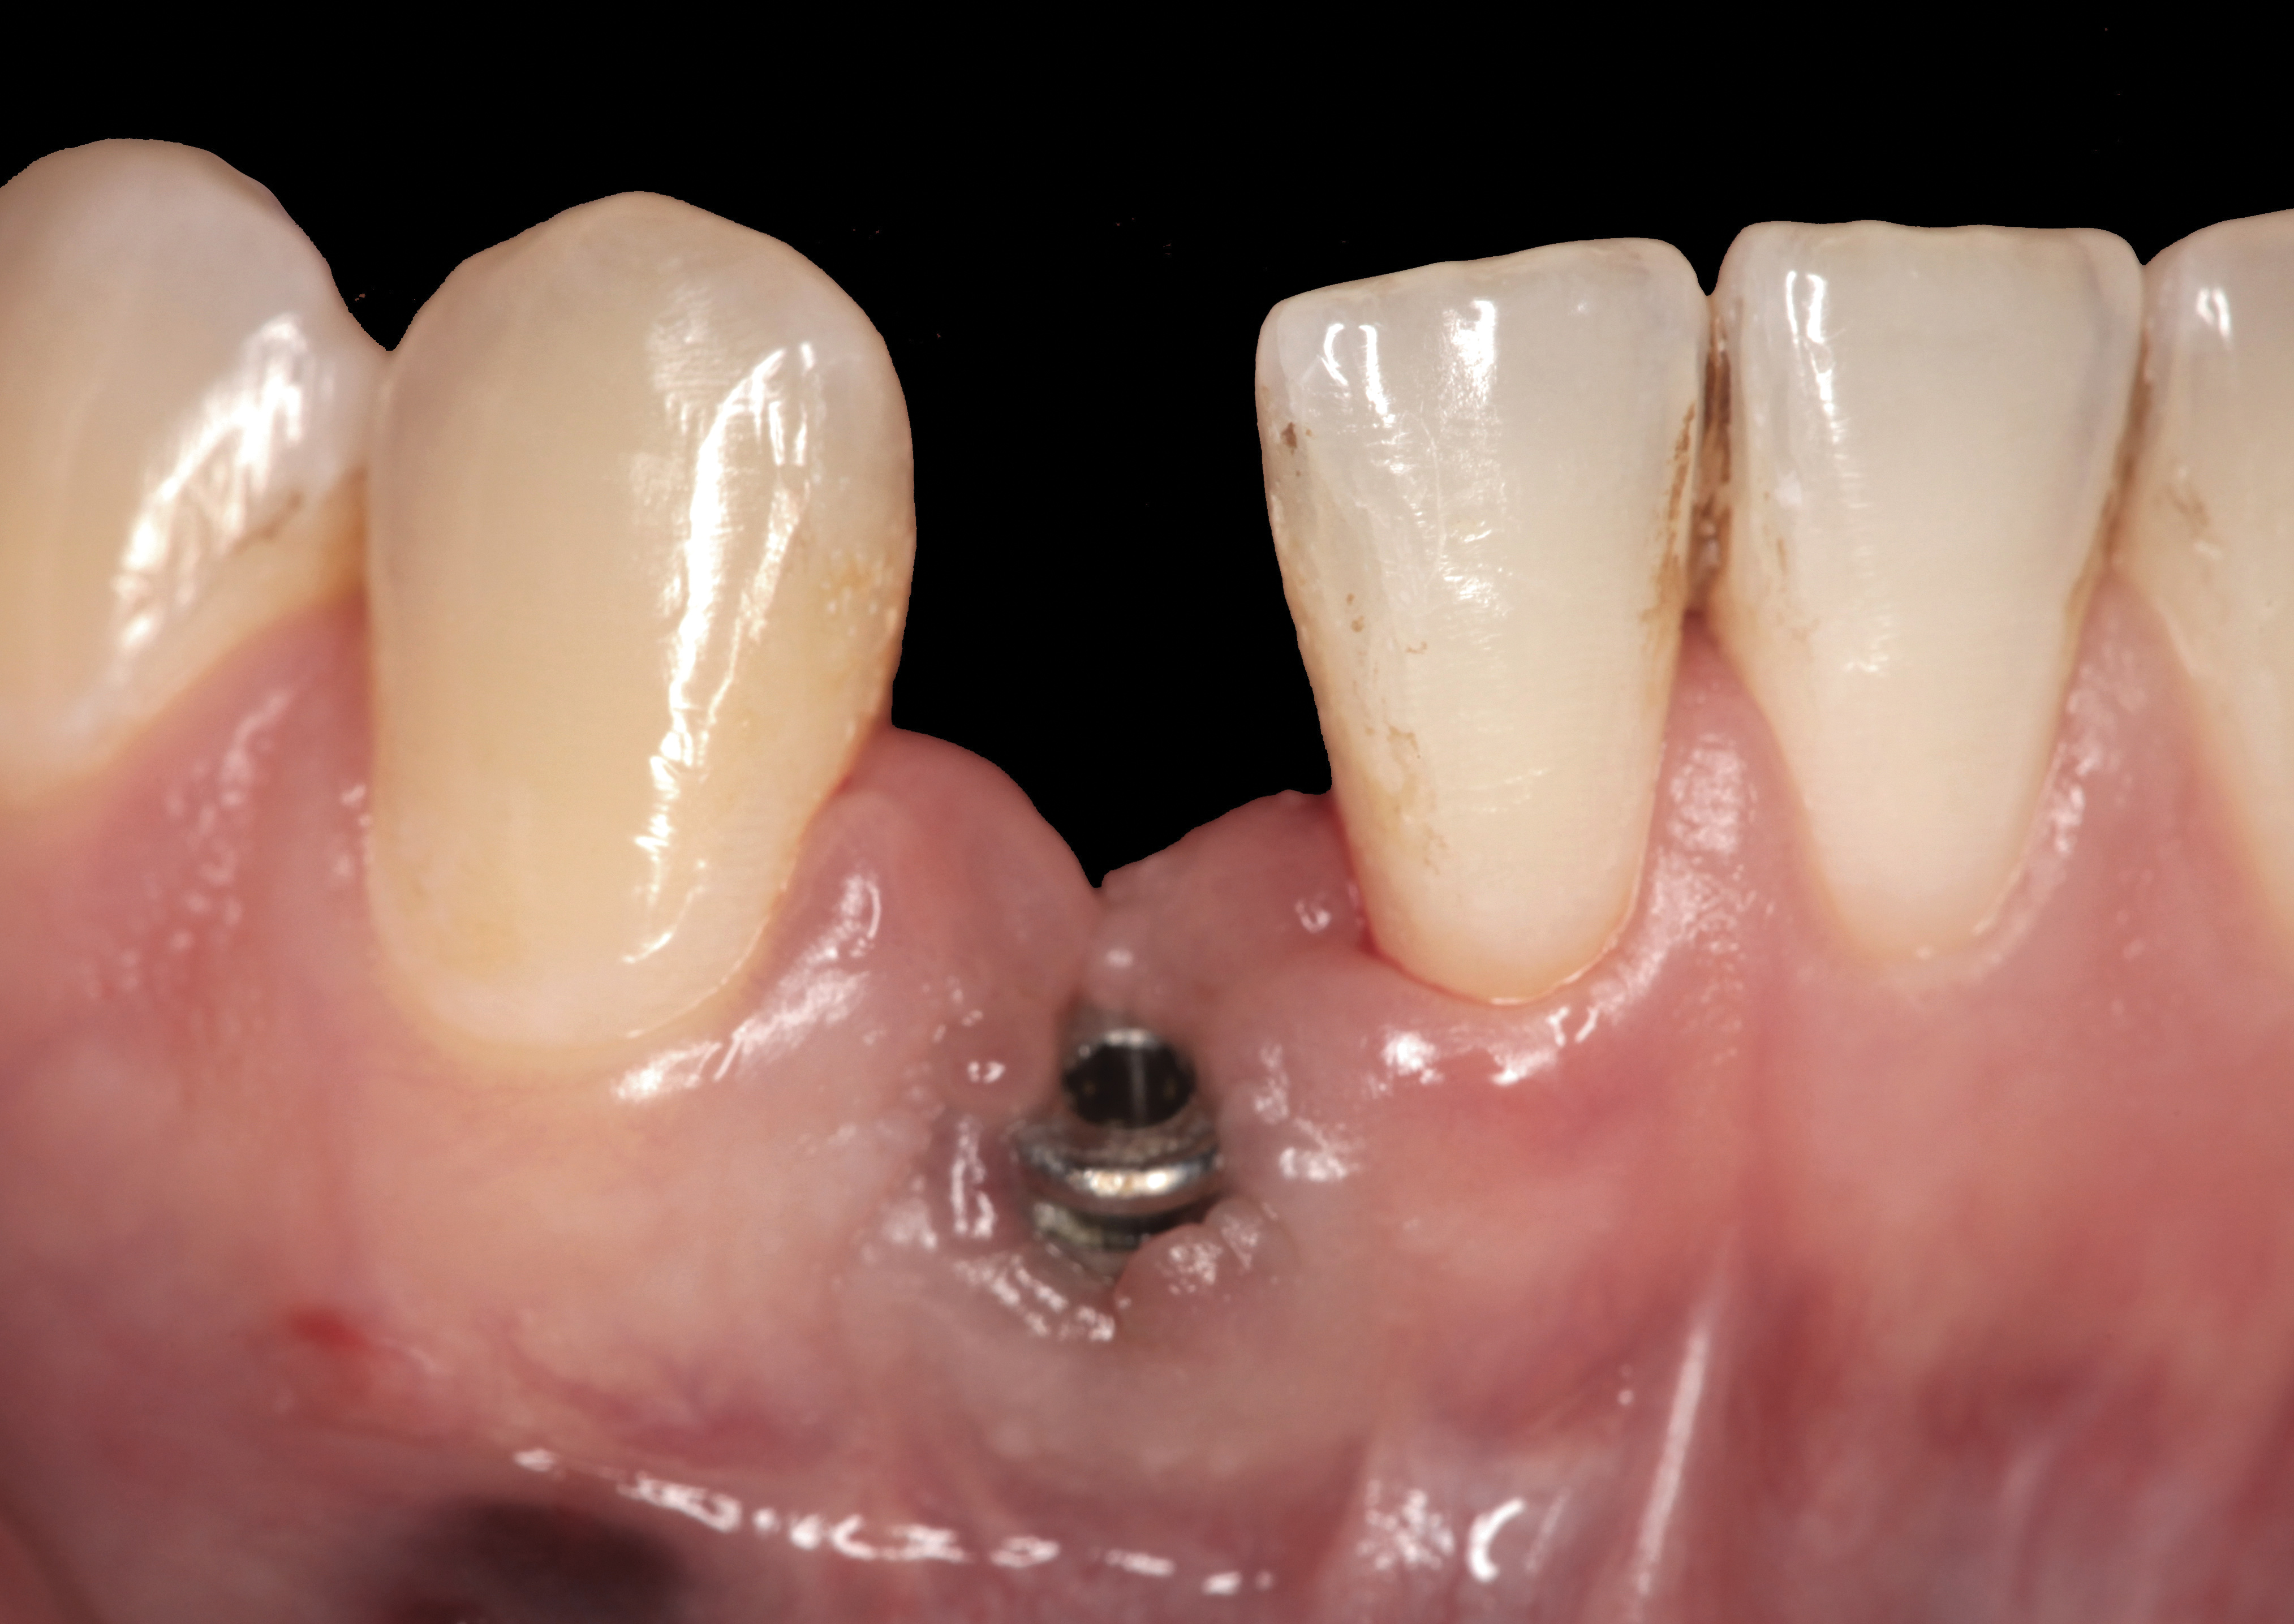

The following case report provides an example of this case scenario: A 24-year-old white male presented with congenitally missing tooth No. 26 restored with a single-tooth cement-retained implant restoration. The implant was placed excessively to the facial aspect of the edentulous site and too shallow, and the periodontal phenotype was thin scalloped (Figure 32). In an effort to mimic the lost midfacial soft tissues, pink ceramics were used as a cosmetic facade. Even though the restoration was not in the esthetic zone, the patient was highly displeased with the esthetic outcome and sought remediation.

The crown and screw-retained custom abutment were removed, and a surgical cover screw was placed into the implant, thereby allowing spontaneous gingival augmentation in situ (Figure 33 and Figure 34). Note that the lingual aspect of the implant site was significantly more coronal than the labial aspect, which was positive because the defect would be limited to a facial–lingual defect. A fixed RBR bridge was cemented on the adjacent teeth and used as a tooth-supported transitional provisional restoration (Figure 35). A few weeks were allotted to let the soft tissue heal and migrate around the cover screw (Figure 36) to see if there would be complete coverage, thereby allowing a soft-tissue augmentation procedure to be performed with primary flap closure as in clinical scenario No. 2. The major obstacle in achieving a positive tissue response was that the implant depth was also deficient because the implant–abutment connection was at the level of the free gingival margin. It was decided that the best treatment option would be to remove the implant. A high-powered reverse-torque device (Fixture Remover Kit, NeoBiotech, www.neobiotechus.com) was used to remove the implant atraumatically (Figure 38 through Figure 41). The implant socket was allowed to heal for several months not unlike an extracted tooth (Figure 42). A new implant was placed in a better position from both a restorative and esthetic perspective (Figure 43), and after a few months of healing, a new crown was made (Figure 44). A satisfactory functional and esthetic result was achieved (Figure 45 and Figure 46) without employing pink porcelain.

Fig 32. A dissatisfied patient presented with significant midfacial recession of implant restoration of tooth No. 26. Pink ceramic material was used unsuccessfully to prosthodontically compensate for the lost midfacial tissue.

Figure 32

Fig 33. Excessive facial angulation of the implant placement shown with an abutment driver in the access screw hole.

Figure 33

Fig 34. A surgical cover screw was placed in an attempt to decoronate the implant and gain soft-tissue coverage in situ.

Figure 34

Fig 36. Two weeks after RBR placement, the soft tissue did not adequately cover the implant. The problem was in poor implant angulation and proper depth to allow the soft tissues to cover over.